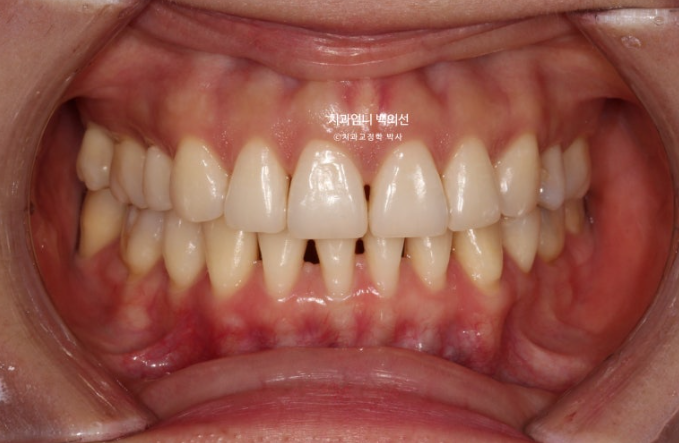

23년 8월, 재교정치료를 위해 내원한 환자분입니다.

블랙트라이앵글과 중심선 불일치가 보입니다.

잇몸이 얇은 편이라 작은어금니 부분에 잇몸퇴축도 보입니다.

얼굴에 비해 위 앞니 중심선이 좌측으로 돌아간 상태인데

원인은 좌우 치아 갯수 차이에 있었습니다.

오래 전 했던 발치교정으로 작은어금니 4개가 없는 상태인데 좌측 첫번째 큰어금니 1개가 추가로 더 없습니다.

상악 좌측에만 치아갯수가 2개나 없는거죠.